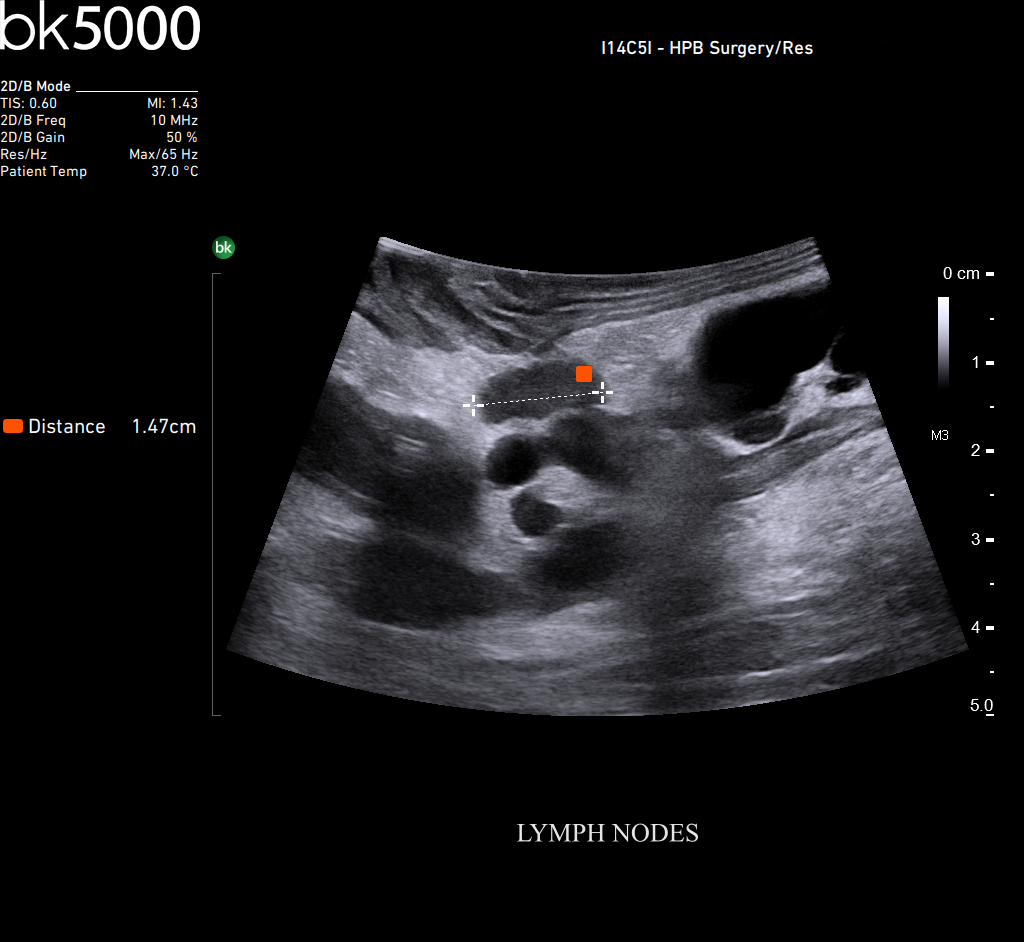

Ultrasound can advance intraoperative surgical procedures by helping you navigate and identify lesions and anatomical structures in real-time. This is particularly important as the data obtained from a preoperative CT or MRI scan can be outdated at the time of surgery.

The bk5000 surgical system provides the highest quality images that allow you to clearly see the margins of a lesion and to determine the best course of action. Using advanced graphics processing technology, this powerful system provides immediate, auto-optimized images that allow you to see the information you need, faster.